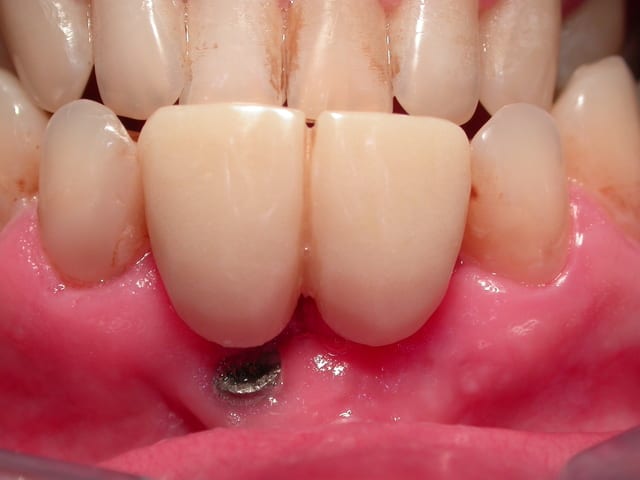

J'ai besoin d'un coup de main pour reconnaitre un implant qui a été posé sur un de mes patients (originaire de république tchèque).

Pour la partie "prothétique" bizarre je vous laisse commenté les photos.

Donc si quelqu'un reconnait le type d'implant et la marque à l'aide de la radio je l'en remercie.